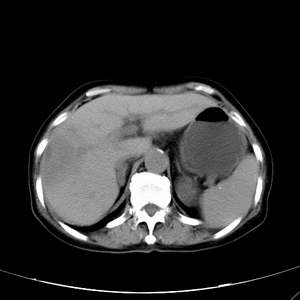

患者,女性,77岁,右上腹胀痛月余。afp正常。ca125升高。即往无肝炎病史。

肝右叶病灶是胆管细胞癌吗?门静脉右支癌栓形成?右侧肾上腺有问题吗?

快进快出符合肝癌表现

最后5幅图片是延时7分钟的。门静脉右前支内有充缺吗?如有,肝血管瘤不好解释。

渐进性强化,中间见沙砾样钙化,首先考虑血管瘤

病灶渐进性向心性强化,延时病灶中心见条片状高密度影,局部见肝包膜回缩征,结合病人无肝炎病史,考虑肝右叶胆管细胞癌,门脉右支癌栓形成。